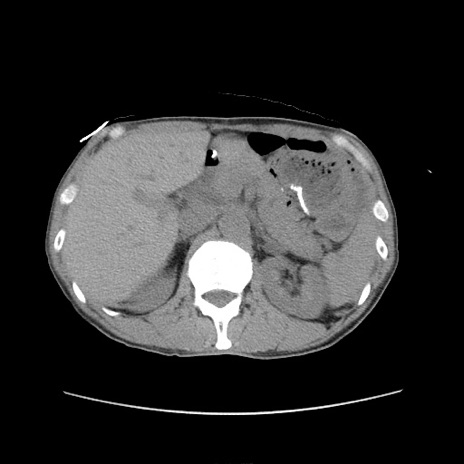

症例11(横断像)

【症例】 60歳代男性

【主訴】 下腹部痛

【現病歴】 本日夜中より下腹部痛の症状認め、受診。

【既往歴】 膀胱癌(膀胱全摘+尿管皮膚瘻術) 、胃癌術後

【身体所見】 BT 35.3℃、PR 58/min、BP 136/98mHg、腹部平坦、軟、腸蠕動音±、ストマ留置あり、左上腹部~正中部に圧痛あり、反跳痛なし。

【データ】WBC 5100、CRP0.01